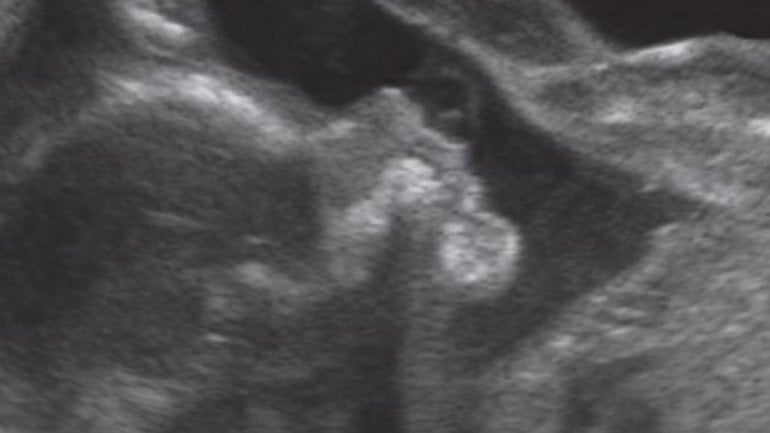

Ultraschall 7. SSW

Links in der Fruchtblase ist der etwa fünf Millimeter lange, wie eine Bohne gekrümmte Embryo sichtbar. Der helle Kreis mit dunklem Fleck über dem Embryo ist der Dottersack, der den Embryo momentan noch mit Nährstoffen versorgt, bis die Plazenta diese Aufgabe voll übernehmen kann.